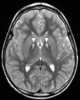

Pantothenate kinase-associated neurodegeneration (PKAN), formerly called Hallervorden–Spatz syndrome, is a genetic degenerative disease of the brain that can lead to parkinsonism, dystonia, dementia, and ultimately death. Neurodegeneration in PKAN is accompanied by an excess of iron that progressively builds up in the brain. [Source: Wikipedia